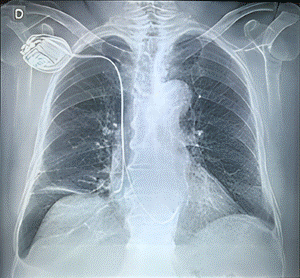

Se decide colocar un implante de marcapaso bicameral, con electrodo auricular en apéndice auricular derecho y con electrodo ventricular en septo ventricular medio, por STB como causa de una miocardiopatía auricular, procedimiento que se efectúa sin ninguna complicación; posteriormente, se realizó una radiografía de tórax, confirmando que el marcapaso y sus electrodos, se encontraban en una ubicación dentro de rangos normales (Figura 4). Fue dado de alta con Apixaban y Bisoprolol.

Figura 4. Radiografía de tórax